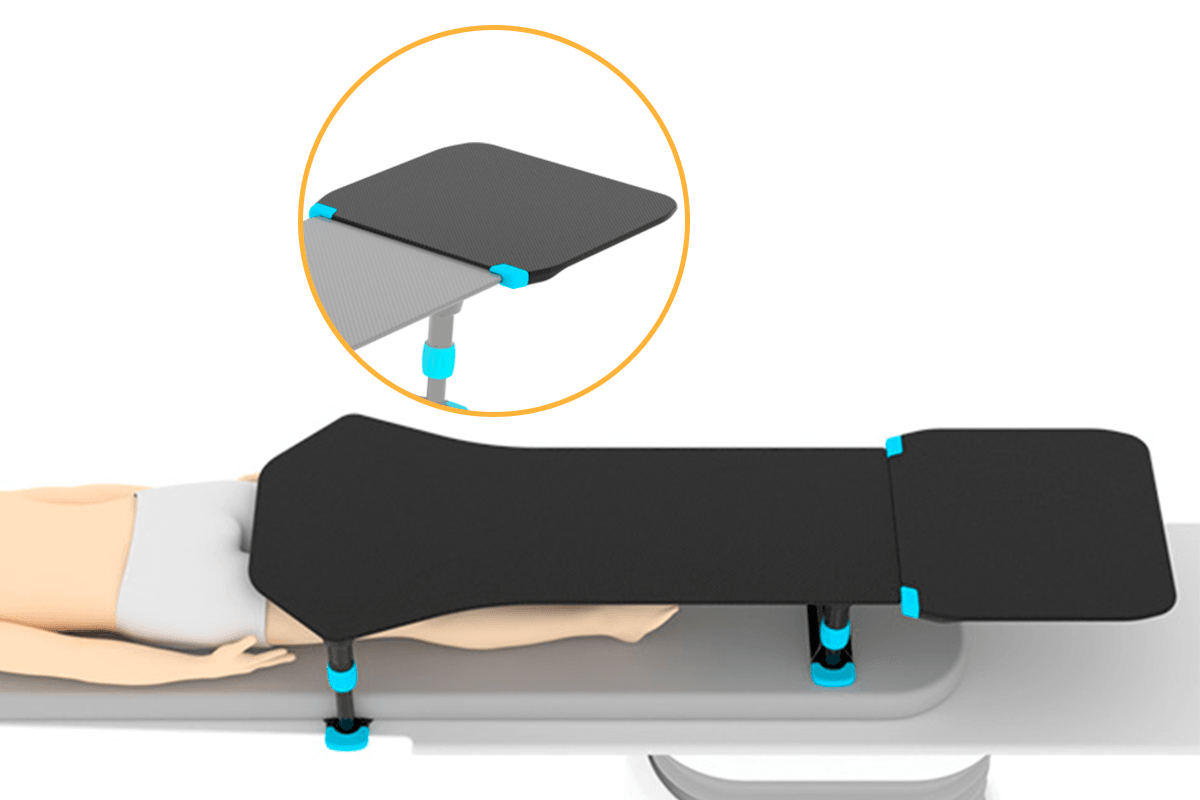

We design medical devices that support patient positioning, clinician ergonomics and procedural workflow in interventional radiology, cardiology and neuroradiology. Devices also available for otology, rhinology and sterilisation.

Interventional RadiologyInterventional CardiologyInterventional NeuroradiologyPeripheral InterventionGeneral Surgical

We focus on quality, performance and reliability to help support better outcomes for both patients and healthcare professionals. Our design engineers interact early with clinicians to ensure our products integrate seamlessly with existing workflows.